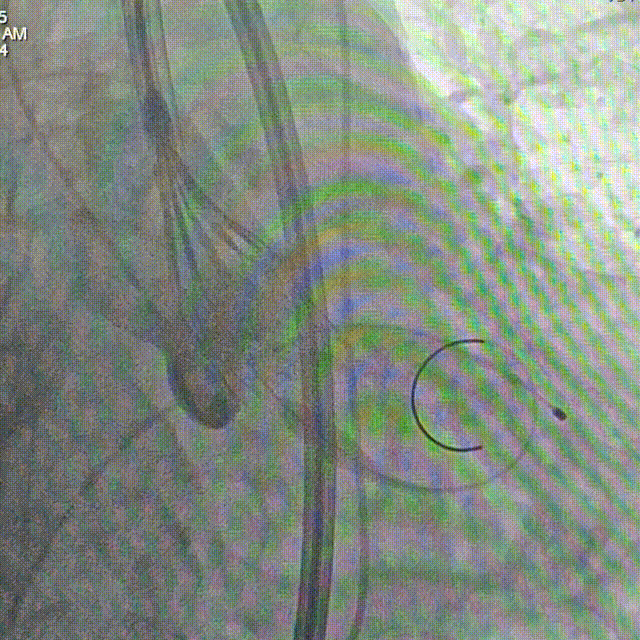

辅入路猪尾根部造影(右窦居中)

瓣膜初始定位

瓣膜开花后造影确认位置

起搏下释放瓣膜至全展开

全展开后造影评估

瓣膜打平造影评估

瓣膜位置可,形态可

脱钩后造影,瓣膜无位移,形态可

弓部剪影,无瓣周漏,升主无损伤